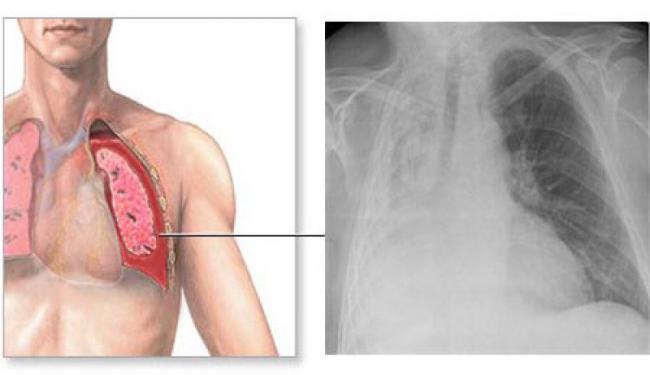

Компрессионный ателектаз

По-другому компрессионное спадение легкого называется коллапсом и возникает при сдавливании газами или жидкостью извне (экссудатом, транссудатом, кровью, фиброзной тканью). Компрессионный механизм развития ателектаза имеет более оптимистичный прогноз при лечении, так как в патогенезе отсутствуют эндобронхиальные факторы — спадение легкого не вызывает выраженной задержки лимфы или полнокровия.

Основными симптомами компрессионного ателектаза являются:

- одышка (возникает постепенно, на фоне какого-либо заболевания);

- затруднение дыхания;

- кашель;

- боль и тяжесть в пораженной доле легких;

- синюшность губ, кожи и конечностей;

- в той части грудной клетки, где происходит спадание – образуется набухание, в том числе и межреберной ткани;

- при совершении дыхательного акта одна сторона грудной клетки заметно отстает.